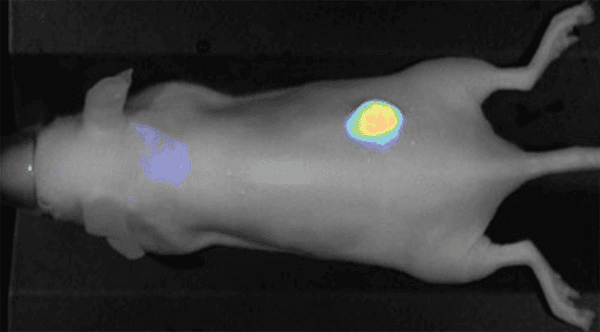

Figure 1. IRDye 800CW EGF imaged 96 h post injection. Image was captured with the Pearl Imager with pseudo-color representing the signal in the 800 nm channel overlaid on the mouse white light image. Research conducted at LI-COR Biosciences.